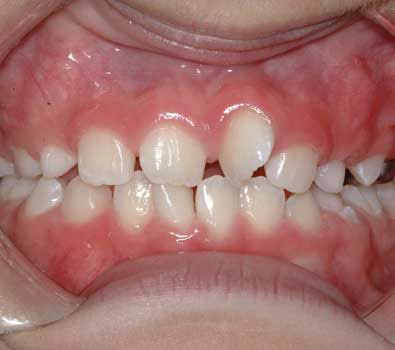

It is normal and even "ideal" for baby teeth to have spacing between each other.

Keep in mind that when permanent teeth erupt, their size will be considerably larger than that of baby teeth. As the baby teeth are lost, the erupting permanent tooth will quickly take advantage of this excess space.

Children who do not have spacing in their primary dentition can have a higher incidence of crowding (crooked teeth) in the permanent dentition.